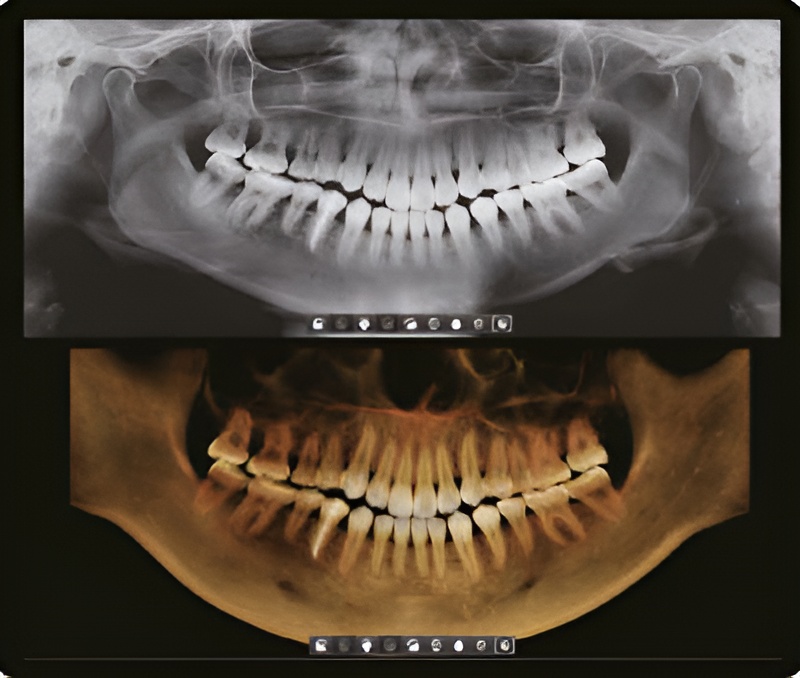

Одно сканирование с Green Smart Vatech позволяет получить не только КТ, но и панорамное изображение. Это означает, что пациенты, которым нужны оба исследования не будут подвергаться дополнительному облучению. Кроме того, оба этих исследования можно просматривать в одной программе.

3D и 2D в одной программе

Одновременный просмотр 2D и 3D-изображений в одной программе помогает пациентам лучше понять о чем говорит доктор, что способствует более быстрому и простому принятию плана лечения.